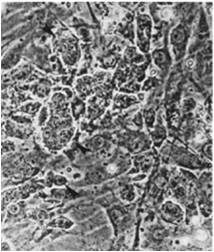

馬丁·約翰·伊文思爵士分離培養(yǎng)的小鼠胚胎干細(xì)胞

詹姆斯·亞歷山大·湯姆森教授分離培養(yǎng)的人胚胎干細(xì)胞